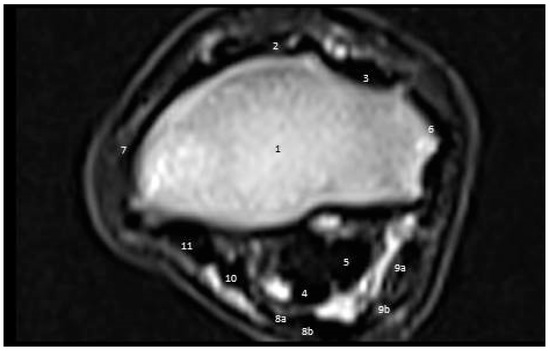

3.3. MRI Findings

3.3.1. First Zone

3.3.2. Second Zone

3.3.3. Third Zone